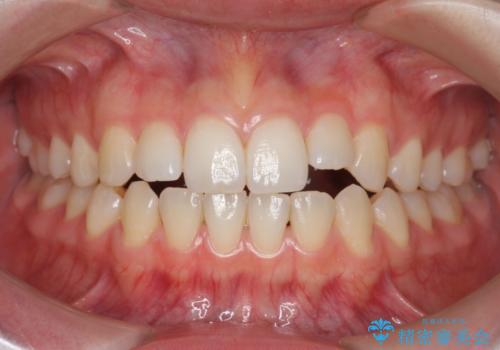

[ 前歯のねじれ・がたつき ] マウスピース矯正

![[ 前歯のねじれ・がたつき ] マウスピース矯正の症例 治療前](https://seimitsushinbi.jp/wp/wp-content/uploads/2024/02/4007c6479f6bce11863dcdd32ed5e39b-500x350.jpg?v=1708502552)

![[ 前歯のねじれ・がたつき ] マウスピース矯正の症例 治療後](https://seimitsushinbi.jp/wp/wp-content/uploads/2024/02/e7a01485e4f4dd0da04705fde4cc34cc-500x350.jpg?v=1708502585)